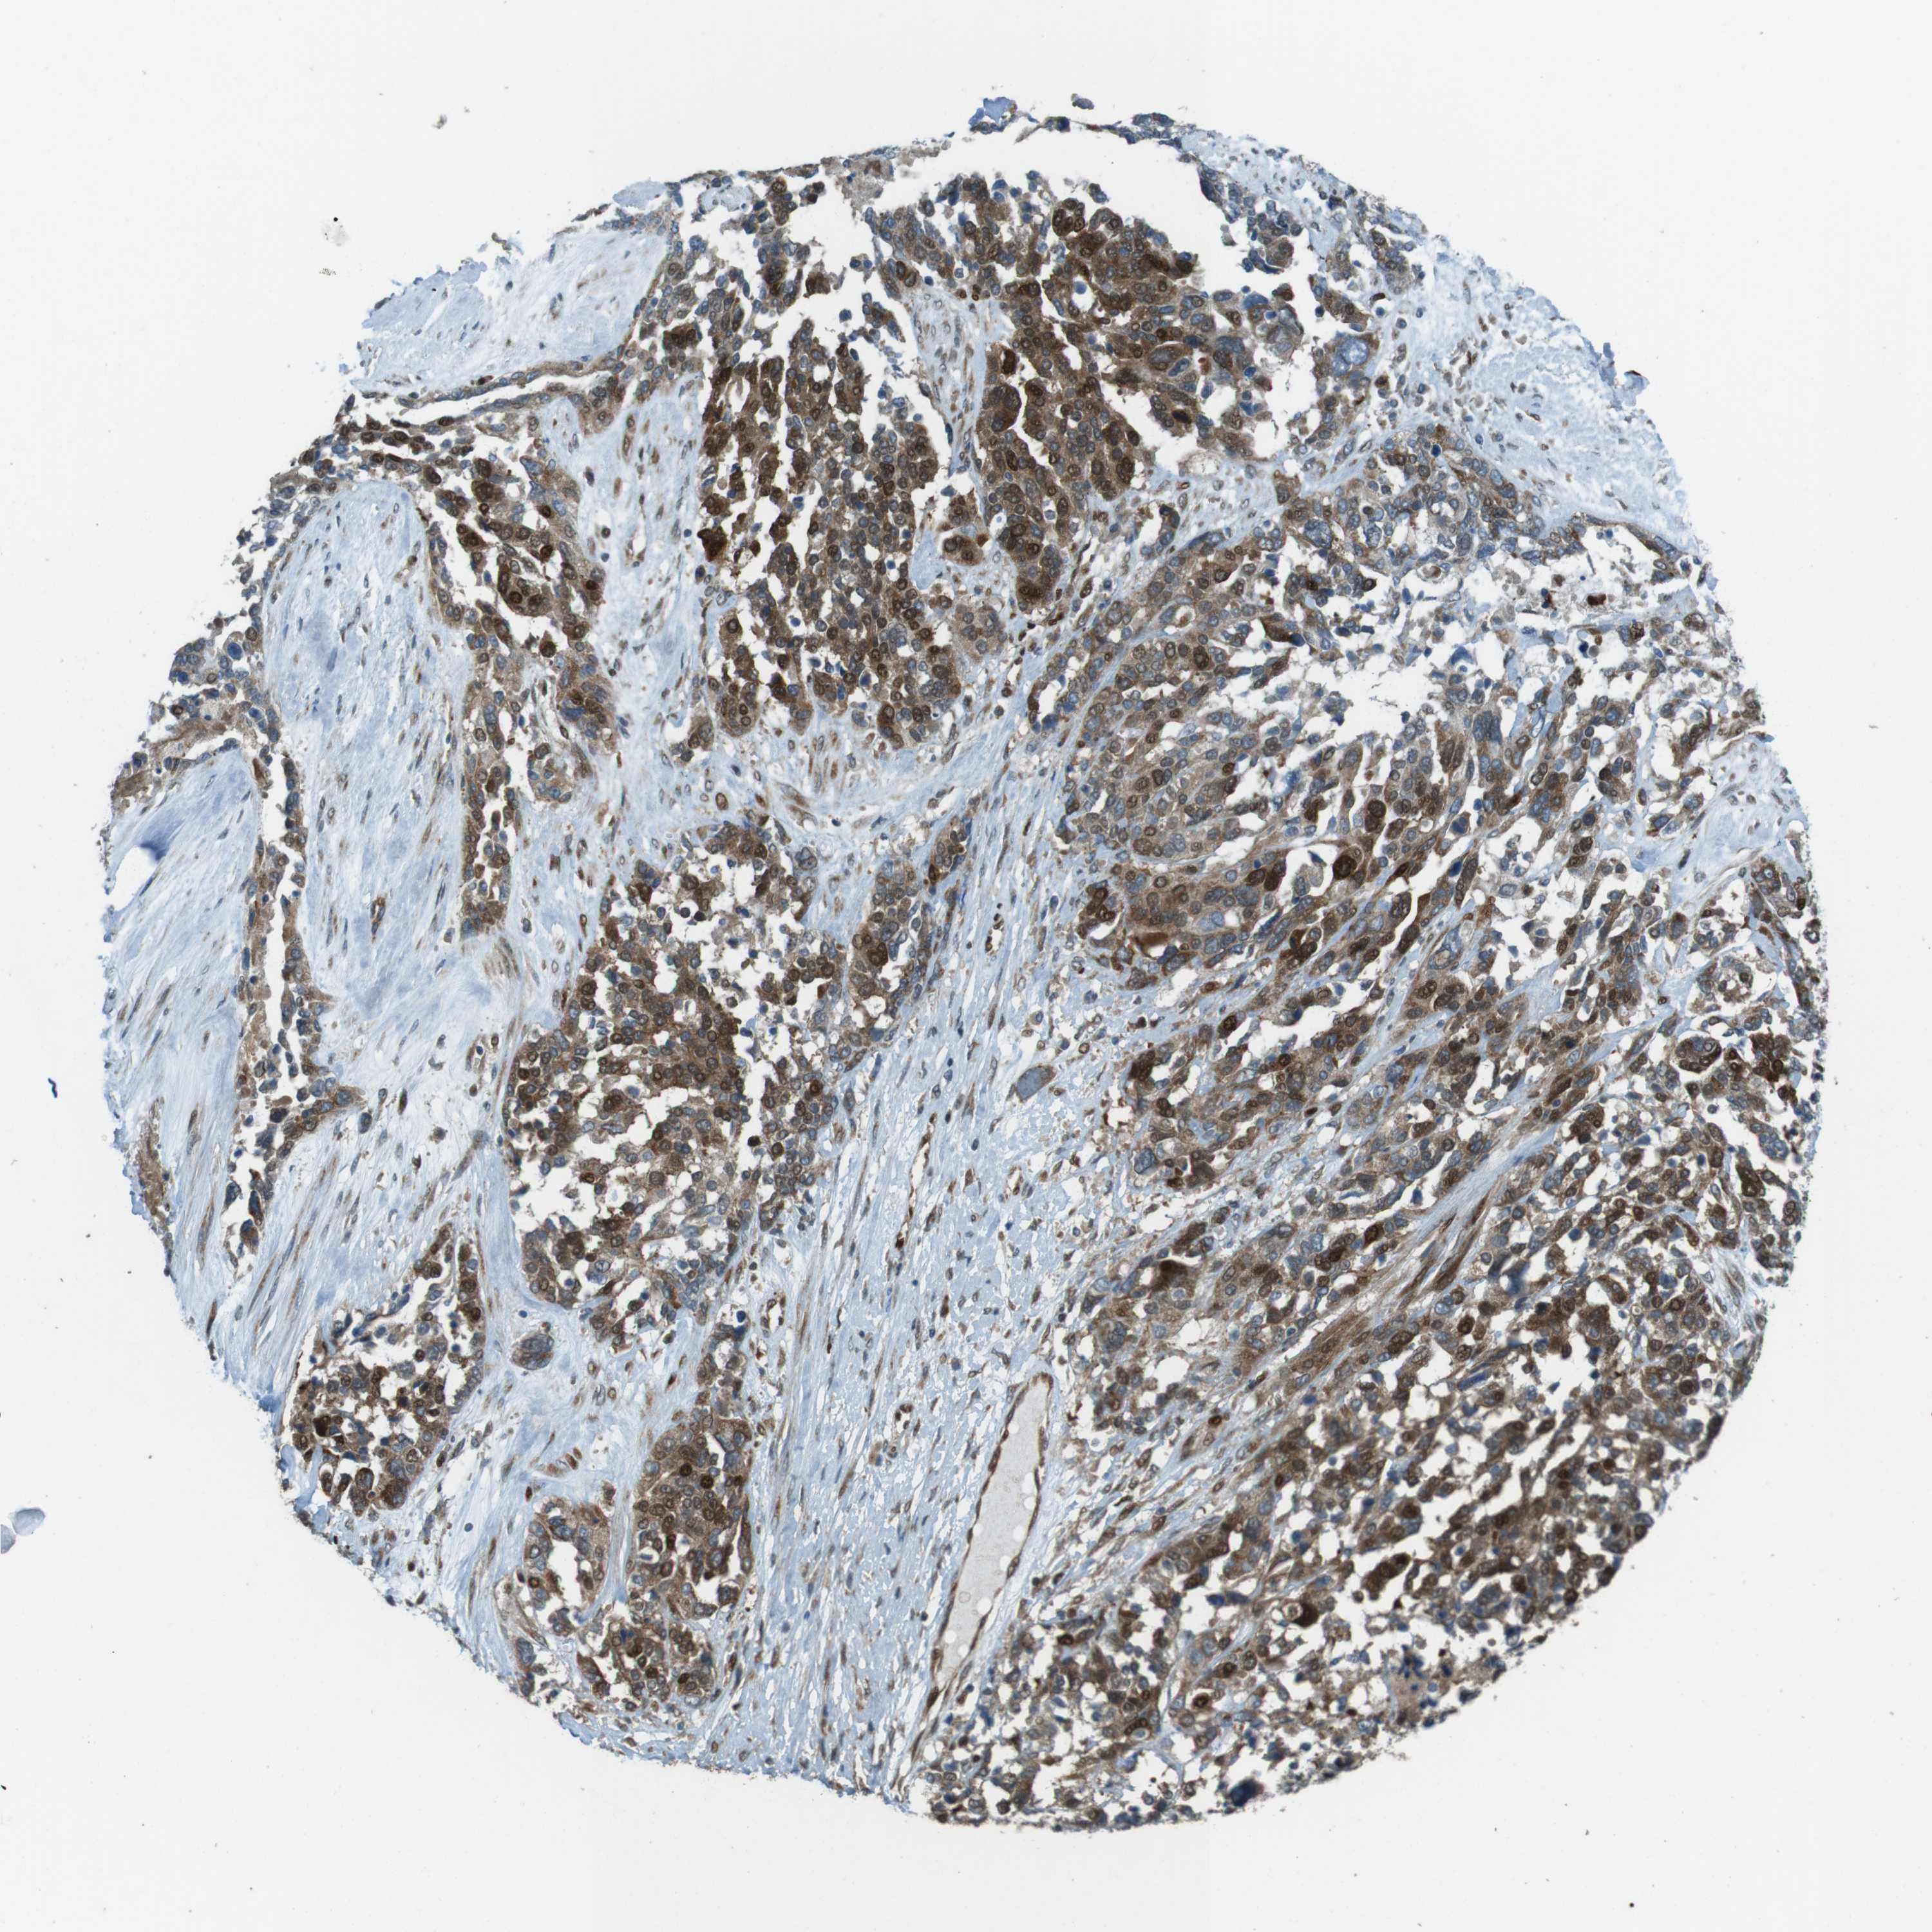

OVARIAN CANCER - Protein expressioni

A mouse-over function shows sample information and annotation data. Click on an image to view it in a full screen mode. Samples can be filtered based on level of antibody staining by selecting one or several of the following categories: high, medium, low and not detected. The assay and annotation is described here.

Note that samples used for immunohistochemistry by the Human Protein Atlas do not correspond to samples in the TCGA dataset.

Antibody stainingi

Antibody staining in the annotated cell types in the current human tissue is reported as not detected, low, medium, or high, based on conventional immunohistochemistry profiling in selected tissues. This score is based on the combination of the staining intensity and fraction of stained cells.

Each image is clickable and will lead to virtual microscopy that enables deeper exploration of all samples and also displays staining intensity scores, fraction scores and subcellular localization as well as patient and tissue information for each sample.

Antibody HPA015705

Staining

High

Medium

Low

Not detected

Intensity

Strong

Moderate

Weak

Negative

Quantity

>75%

75%-25%

<25%

None

Location

Nuclear

Cytoplasmic/membranous

Cytoplasmic/membranous,nuclear

Cystadenocarcinoma, serous, NOS

Carcinoma, endometroid

Cystadenocarcinoma, mucinous, NOS

Carcinoma, NOS